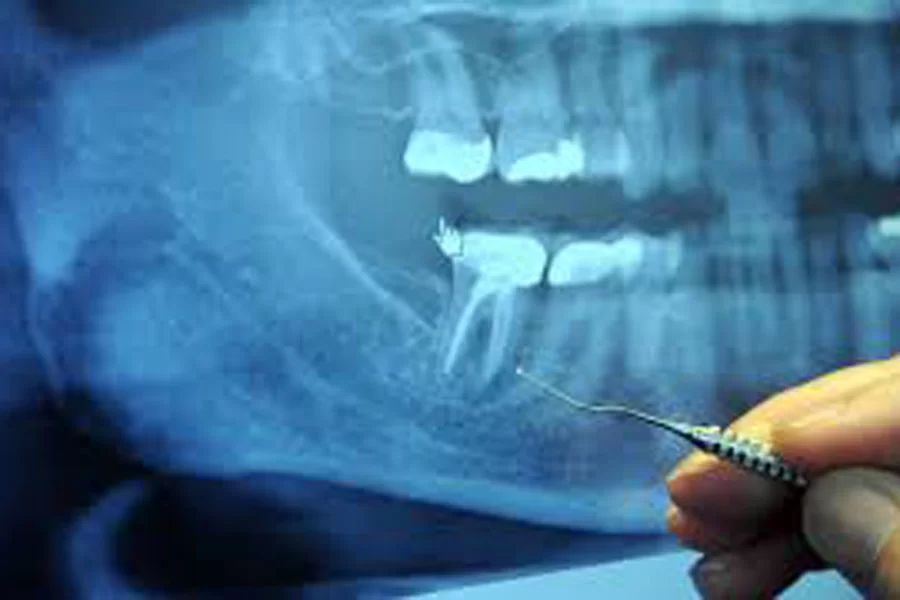

歯科用CT・レントゲンの安全性

当院のデジタルレントゲンやCTは、被ばく量が極めて低く、撮影部位もお腹から離れています。

さらに防護エプロンを着用していただくことで、お腹の赤ちゃんへの影響は限りなくゼロに抑えられます。

(※それでも不安な場合は、無理な撮影は行わず、視診を中心に対応します)